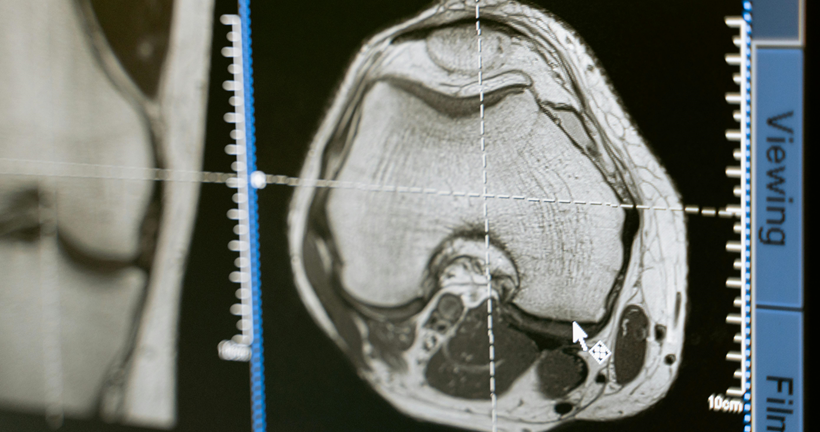

La presentación sintomatológica de la disfunción frontal dependerá de si la afectación predominante inmiscuye a regiones del cíngulo u orbitales. Además, las afectaciones de las funciones ejecutivas dependerán del daño en la corteza dorsolateral. Buscamos describir la relación existente entre la atrofia cerebral identificada en estudios de resonancia magnética estructural, PET-FDG y su implicación cognitiva sobre los pacientes con DFTvnf.

Como resultados en relación con los estudios analizados, se encontró que solo el 15% de artículos mantienen una correlación de áreas anatómicas - cognitivas, además se encontraron alteraciones en los dominios de atención, memoria y funciones ejecutivas mientras que los hallazgos de atrofia cerebral se localizan en áreas frontales, el cíngulo e ínsula.